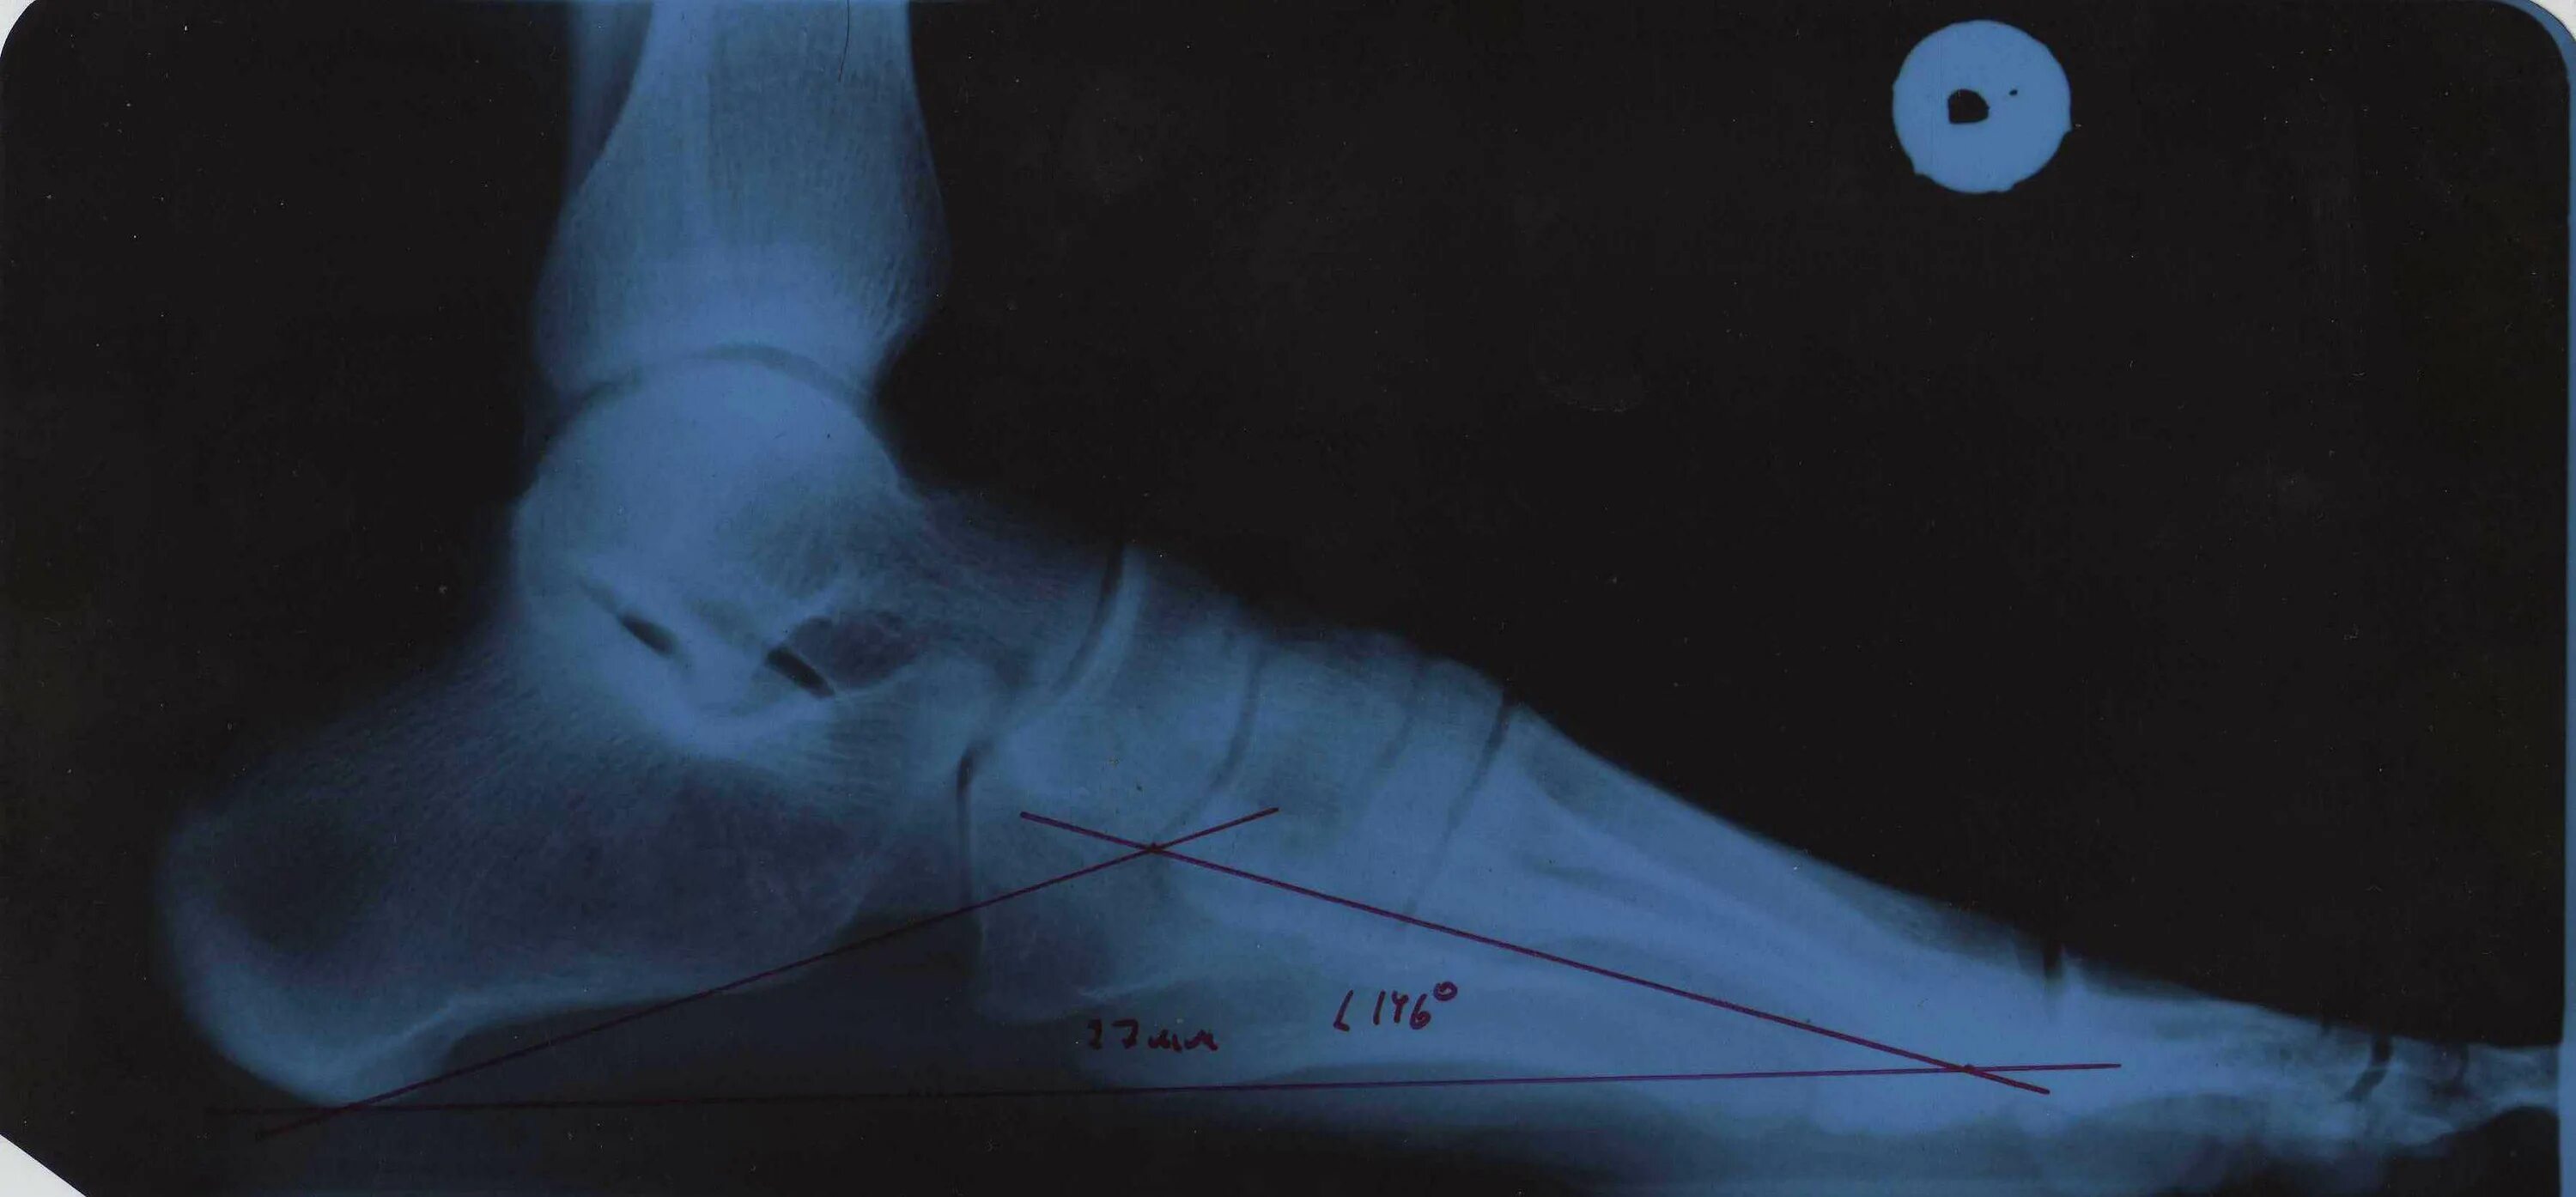

Свод стопы 3 степени. Угол свода стопы при плоскостопии 1 степени. Угол продольного свода стопы 160 градусов. Продольная плоскостопия рентгеноморфометрия. Высота свода стопы 17 мм , угол свода 155 градусов.